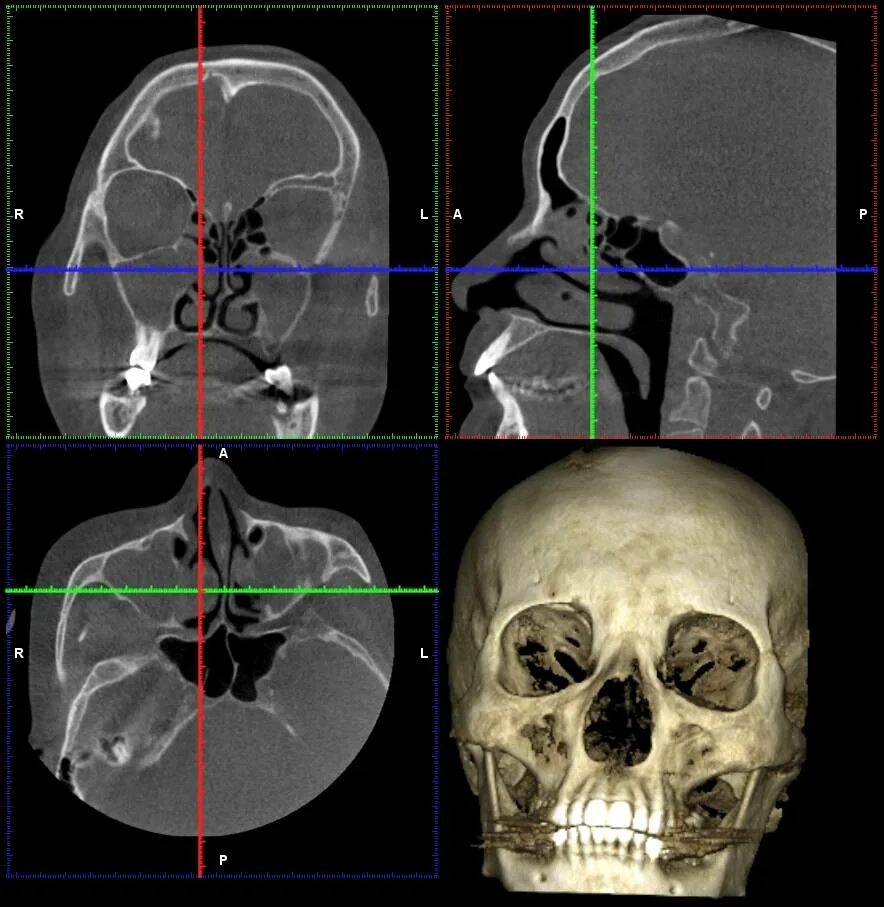

Опасно делать кт